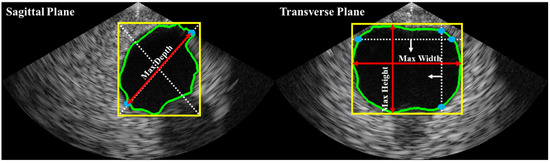

Bladder volume is typically estimated based on shape coefficients and measurements of height, width, and depth on two different planes (i.e., sagittal and transverse). In this study, as illustrated in Figure 4, depth was estimated on the sagittal plane, while height and width were estimated on the transverse plane. The bladder volume was then calculated using Equation (1), where c is a constant determined by the shape of the bladder region (e.g., 0.52 for a spherical shape, 0.7 for an unknown shape [21]).

Figure 4.

Automated axes detection for estimating bladder height, width, and depth from biplane ultrasound images. The bladder ROI dimensions were obtained by calculating the minimum enclosing bounding box (yellow line). In the sagittal plane, the greater distance between two intersections (blue dots) of the bounding box’s diagonal line (white dashed lines) with the bladder ROI contour (green line) was used to estimate depth. The red arrow lines represent the estimated depth. In the transverse plane, the maximum distances of the vertical and horizontal intersections were used to estimate height and width, respectively.